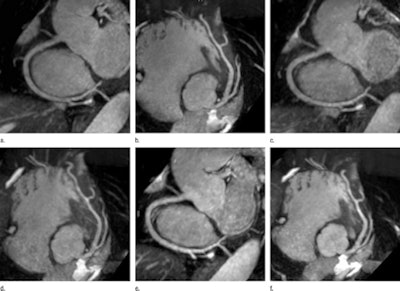

|  |

| Unenhanced 1.5-tesla whole-heart coronary MR angiography in a healthy subject shows results with a five-channel cardiac coil and a SENSE factor of 2 (a, b), a 32-channel coil and a SENSE factor of 2 (c, d), and a 32-channel coil and a SENSE factor of 4 (e, f). Images courtesy of Radiology. |

The two readers found no significant differences in image quality among the three protocols.